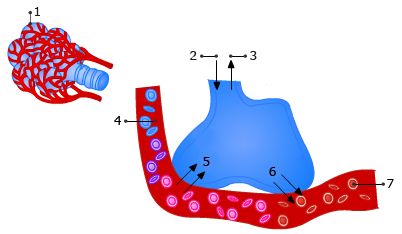

Gaswisseling

Kies de juiste bijschriften bij de nummers.

-

-

-

-

-

-

-